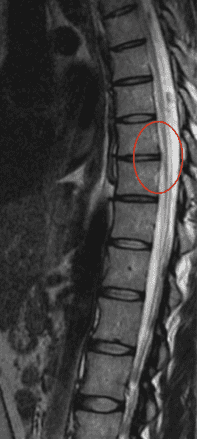

Przepuklina lub wypuklina dysku piersiowego jest raczej rzadkim schorzeniem, głównie ze względu na obecność w tym odcinku klatki piersiowej, która wspiera, usztywnia i odciąża kręgosłup oraz ponieważ rzadko kiedy wykonujemy czynności, które wymagają oparcia w tym odcinku.

W przypadku podejrzenia schorzenie kręgosłupa, Jądrowy rezonans magnetyczny (MRI) lub Tomografia komputerowa (CT), mogą wykazać zmiany związane z objawami.

-Sprawa nr 12534